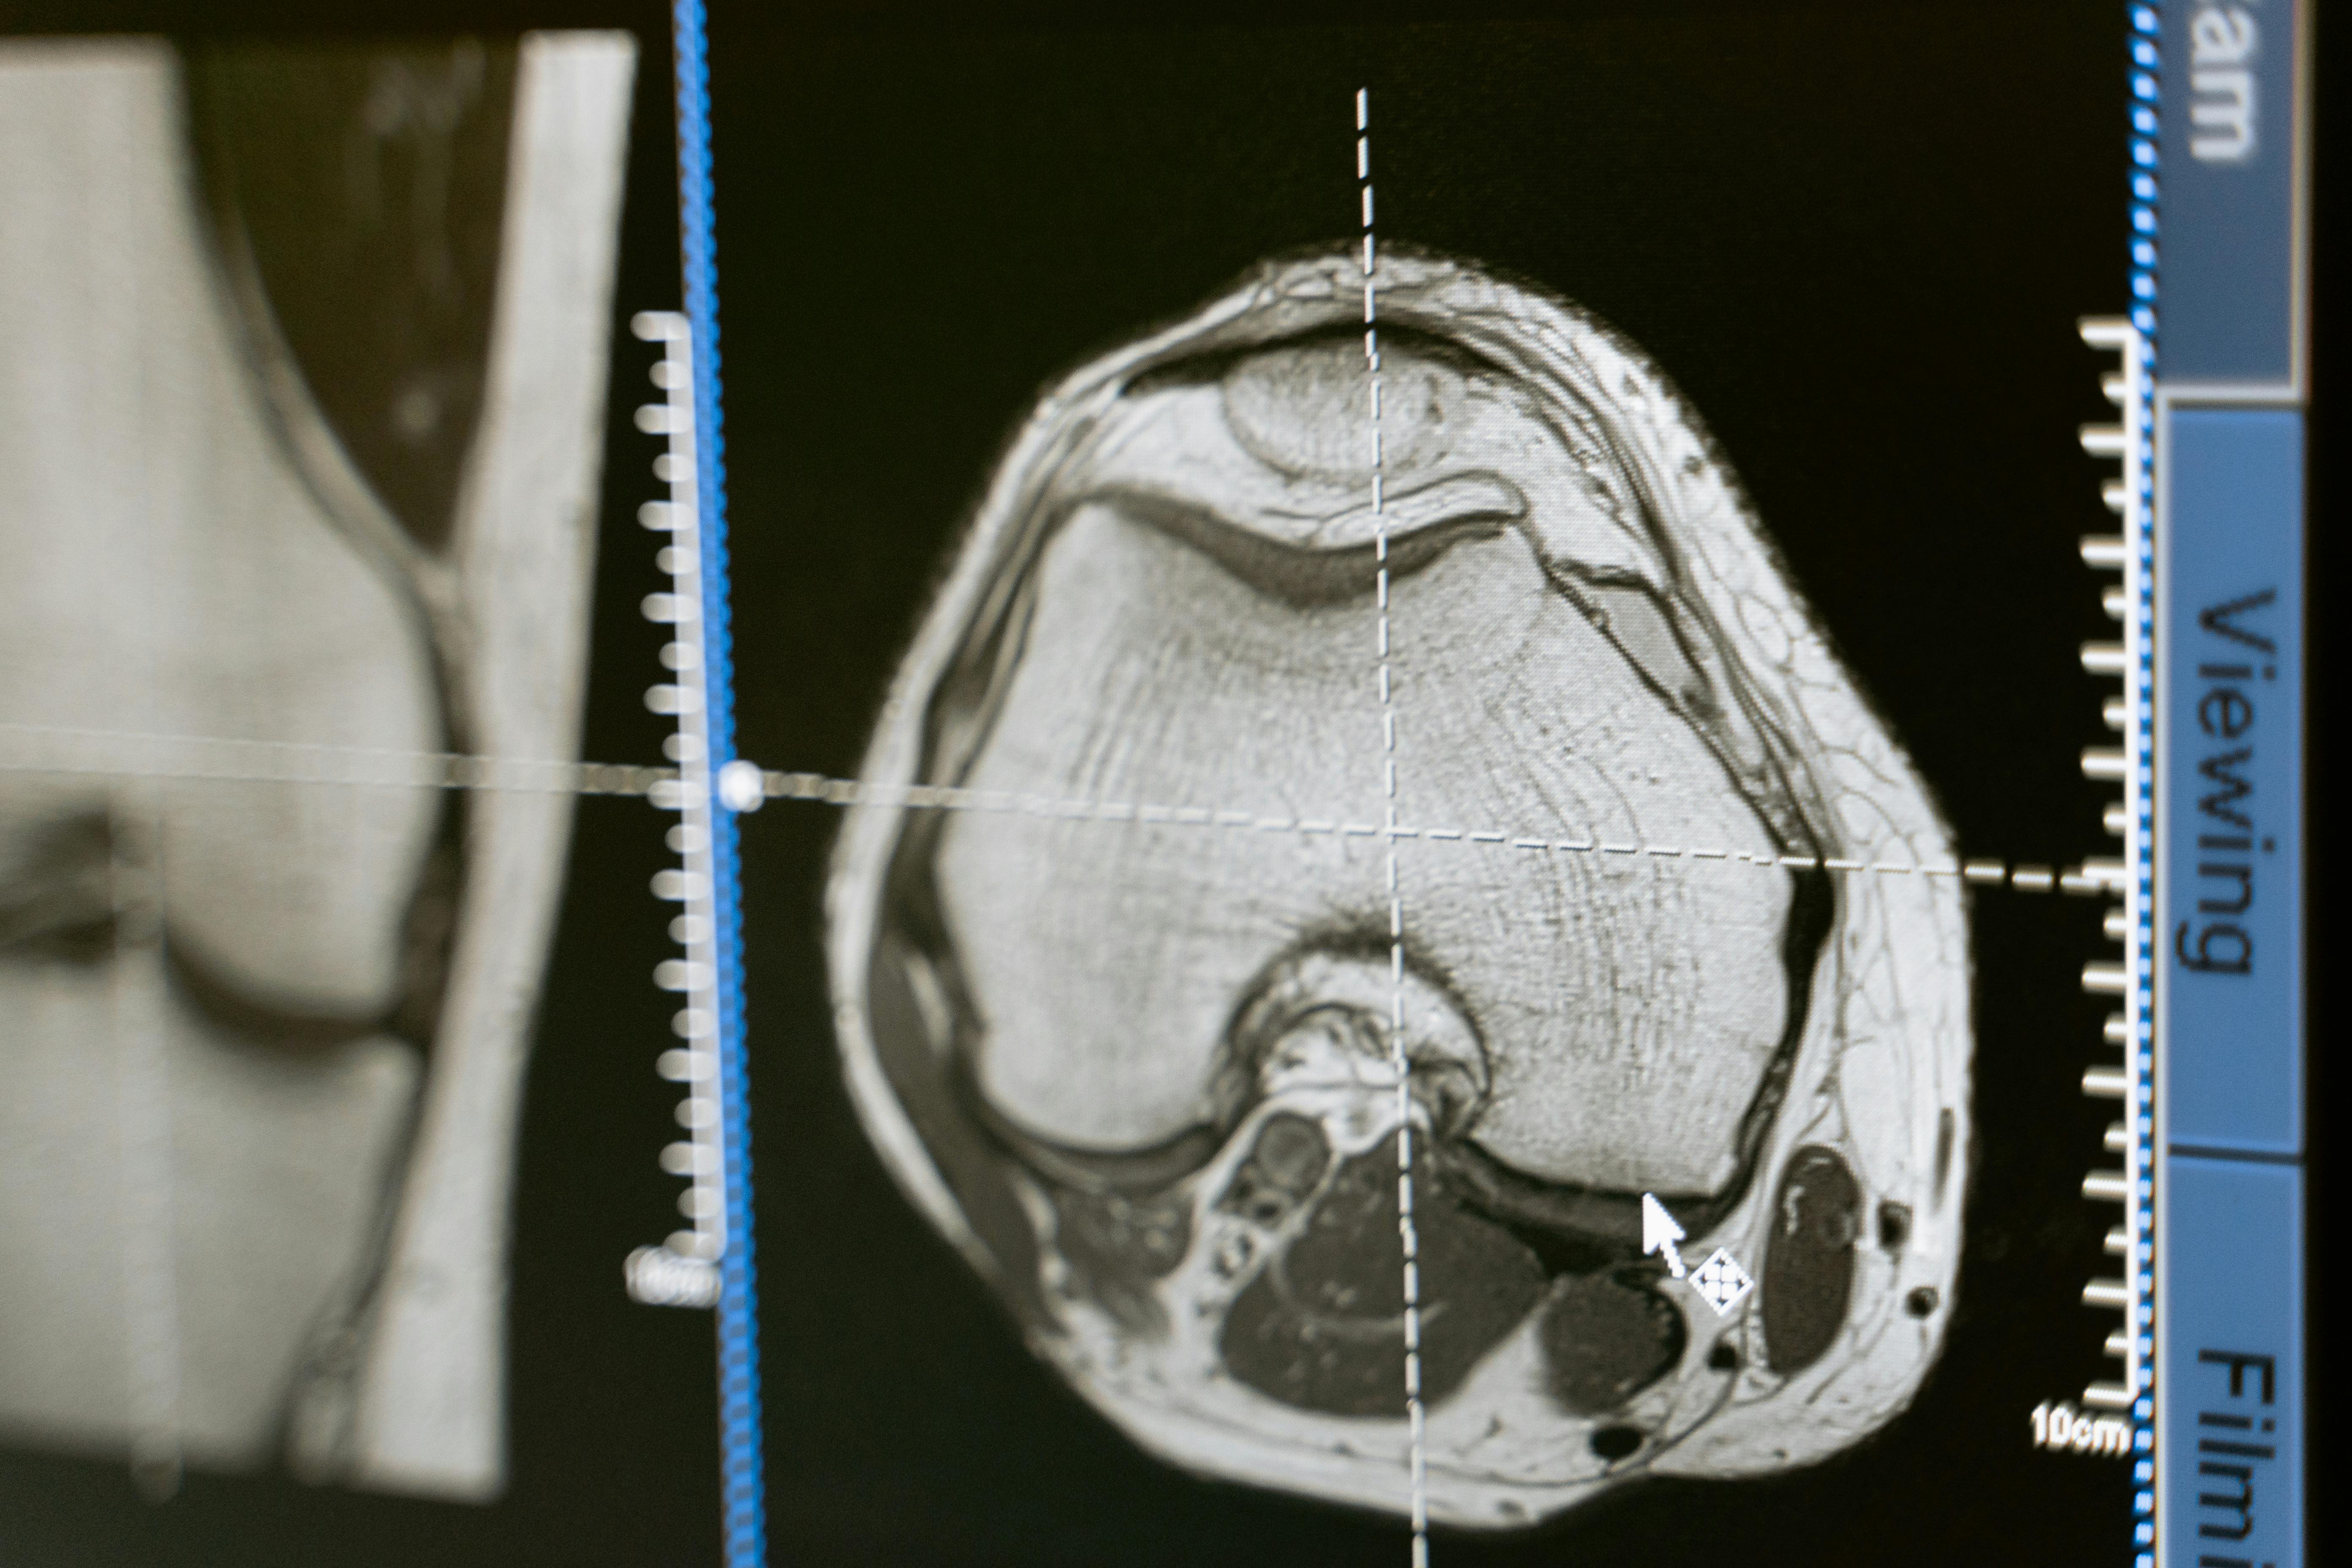

대장내시경은 한쪽 끝에 매우 작은 초소형 카메라가 달린 유연한 관을 이용하여 대장과 소장의 말단 부위를 사진과 영상을 이용하여 내부를 직접 관찰 및 검사를 할수 있습니다. 45세 이후에는 5년마다 대장내시경을 받고, 용종이 있다면 1~3년 단위로 재검사를 해야 합니다. 만약 가족력이 있다면 30대 후반부터 검사를 하는 것을 권합니다. 검사 전에는 병원의 안내에 따라 장 세척을 철저히 하고, 검사 후에는 하루 정도 유동식을 섭취하며 무리한 활동을 피하는 것이 중요합니다. 증상이 없는 대장암은 초기증상이 없이 대부분 용종에서 시작됩니다. 대장 내시경을 통해 암으로 발전할 가능성이 있는 선종을 미리 확인 하여 대장암 발생률을 효과적으로 낮출 수 있습니다. 이것 또한 조기 발견 시 대장암 발생율을 90%까지 낮출 수 있기 때문에 정기 검진은 필수입니다.